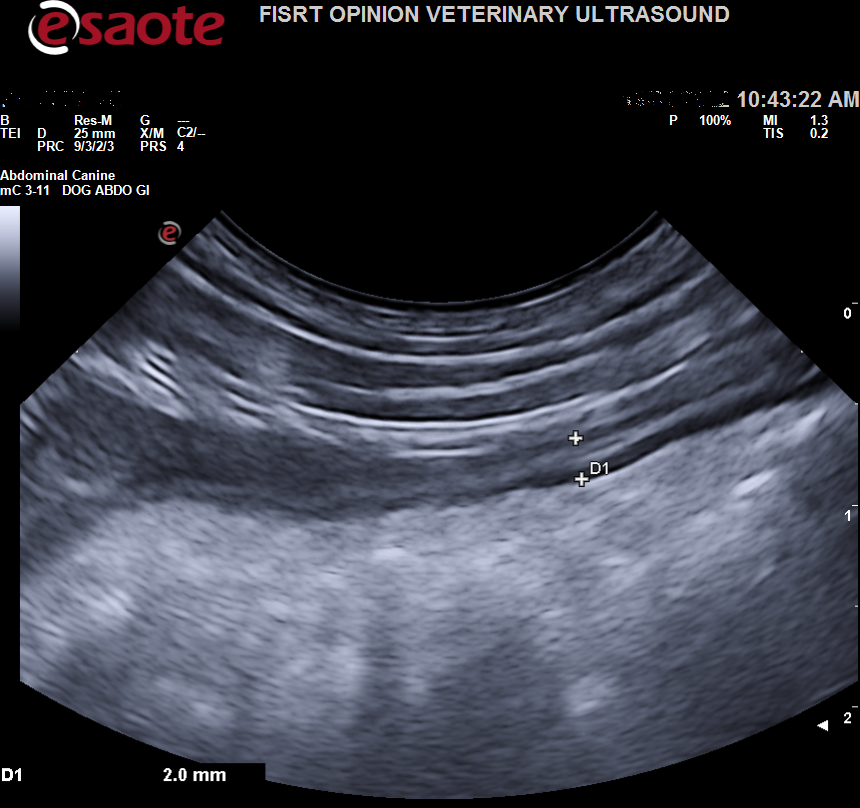

Images from the Sigma